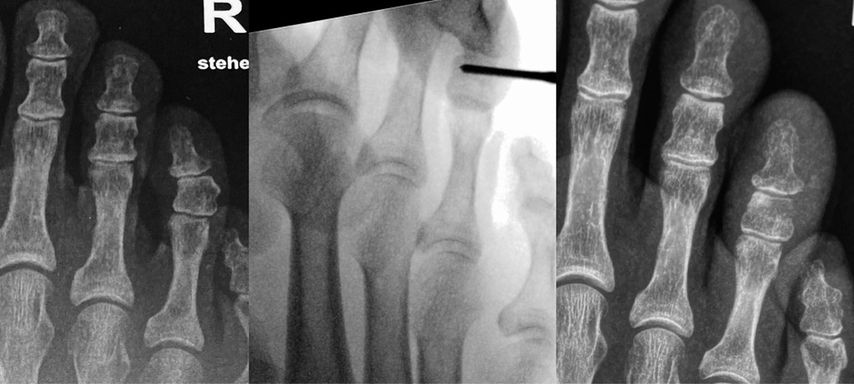

Unter der Generation 3 werden Modifikationen der Chevron-Osteotomie zusammengefasst, die per Stichinzision mittels Fräse durchgeführt werden. Fixiert wird mit kopflosen Schrauben. Redfern und Vernois bevorzugen hier sehr lange 3,5 mm- bzw. 4,0 mm-Schrauben, die von proximal medial am Metatarsale 1 in das Köpfchen eingebracht werden.2 Gerhard Kaufmann führt ebenfalls eine Osteotomie mit Fräse durch, fixiert aber weiter distal ähnlich wie bei der klassischen Chevron-Osteotomie (Abb. 1).

Vernois und Redfern präsentierten 100 Füße mit einem von 95% der Patienten als sehr gut und gut beurteilten Outcome.2 Gerhard Kaufmann publizierte 2020 seine Ergebnisse der minimalinvasiven Chevron-Osteotomie im Vergleich zur offenen Chevron-Osteotomie,6 mit Kontrollen nach 6 und 12 Wochen sowie 9Monaten und 5Jahren. Es gab keine Korrekturverluste zwischen den kurzfristigen und langfristigen Kontrollen, der Vergleich der Gruppen ergab keine Unterschiede. Jowett und Bedi analysierten 2017 die Lernkurve der minimalinvasiven Chevron-Osteotomie.7 Sie stellten eine steile Lernkurve fest. Palmanovich beschrieb 27 Patienten als notwendig, um die Lernkurve zu verlassen.8 Wenn die Technik beherrscht wird, so sind auch schwere Hallux-valgus-Fehlstellungen korrigierbar und vor allem Wundkomplikationen sind selten.

Auch die Akin-Osteotomie kann sehr einfach minimalinvasiv durchgeführt werden. Sie wird entweder mit einer Schraube oder aber einfach mit Tapes für 4 Wochen stabilisiert (Abb. 2).